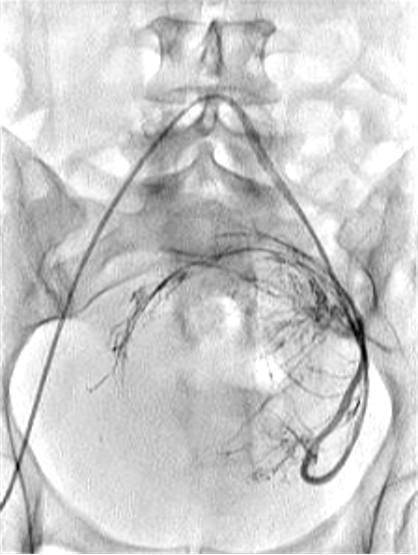

所有年龄超过 40 岁的患者, 卵巢受损 14%-43% 研究中闭经发生率(15%)与单纯UAE报告相似,可能与患者年龄(≥45岁)及卵巢储备自然下降有关。 ![]() 50岁,长期因子宫肌瘤导致月经出血过多,痛经和贫血。 子宫肌瘤栓塞术前,显示双侧子宫动脉发育不全,子宫肌瘤双侧卵巢动脉。 经皮股动脉穿刺双侧卵巢动脉栓塞,先500μm-700μm emboSphere 微球 术后4周,和6月的中短期随访,月经正常,子宫容积减少,贫血纠正,无卵巢功能衰竭。但看起来非灌注容积较少。 术后9月,由于子宫肌瘤持续存在,患者自己希望绝经,行全子宫和双侧卵巢切除术 术后病理,子宫内可见栓塞微粒伴有坏死,卵巢内也见栓塞微粒,但卵巢功能未受损。